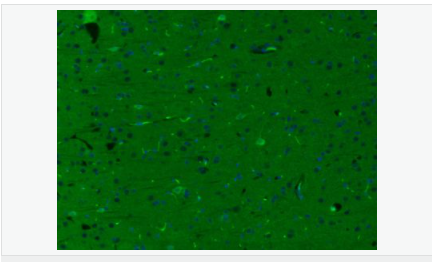

| 产品应用 | WB=1:500-2000 ELISA=1:5000-10000 IHC-P=1:100-500 IHC-F=1:100-500 ICC=1:100-500 IF=1:200-800 (石蜡切片需做抗原修复) not yet tested in other applications. optimal dilutions/concentrations should be determined by the end user. |